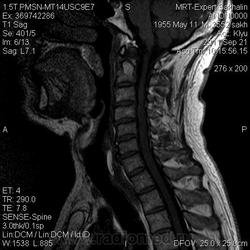

Направительный диагноз: заболевание правой лобной доли, травматический перелом латеральных масс С4 слева, травматическая миелопатия С3-С4, тетрапарез.

Краткий анамнез заболевания, жалобы: беспокоит нарушение чувствительности и координации движений верхних конечностей, в анамнезе - дтп (10.07.11), ушиб спинного мозга шоп.

образование правой лобной доли, возможно фиблиллярная астроцитома.

Компрессионная миелопатия на фоне грыжи диска в сегменте С3/С4.

Насчёт травмы - сомнительно, и где жироподавление? где корональные проекции?

инфильтративно растущая опухоль  в правой лобной доле , миелопатия -как посттравматического характера так и на фоне хроническо компрессии дискоостеофитными комплексами  С3-С5.

Тут стеноз позвоночного канала на шейном уровне,  миелопатия на уровне С3-С4, а вот травматического ли генеза грыжа - не понятно.

Кстати, на фоне таких изменений, миелопатия не обязательно будет компрессионной. Как грамотнее писать? просто миелопатия? Бывает, что после травм смотрим пациентов и там определяются подобные изменения при сохранении просвета позвоночного канала, но происходит травматизация СМ о дегенеративно измененниые позвонки (остеофиты).

травма была 10.07 ,  на настоящий момент очаг контузии выглядел бы иначе. То , что есть, это диффузная опухоль  с поражением белого и серого вещества  с со стиранием границ между этми структурами , извилины выглядят утолщенными. Согласна с коллегой Евгением-похожа на фибриллярную астроцитому.